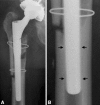

Background: The transfemoral approach is an extensile surgical approach that is performed routinely to facilitate cement and implant removal and improve exposure for revision stem implantation. Previous studies have looked at clinical results of small patient groups. The factors associated with fixation failure of cementless revision stems when using this approach have not been examined.

Results: The average Harris hip score improved from 45.2 (± 14.02) preoperatively to 83.4 (± 11.86) at final followup. Complete radiographic bony consolidation of the osteotomy site was observed in 95% of patients. Dislocations occurred in 9% of patients. Four revision stem fixation failures were observed, all occurring in patients with primary three-point fixation. Three-point fixation was associated with short osteotomy flaps and long revision stems.

Conclusions: The transfemoral approach is associated with a high rate of osteotomy flap bony healing and good clinical results. When using the transfemoral approach, a long osteotomy flap should be performed and the shortest possible revision stem should be implanted.